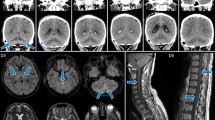

TBEV VBT infections cause predominantly moderate to severe TBE

None of the patients with VBT infection of which clinical scores were available presented with mild disease but suffered from moderate (75%) and severe (25%) TBE based on the severity score (Fig. 1A, B). In contrast, 19 out of 54 (35%) unvaccinated TBE patients had mild TBE (Fig. 1A, B). The severity score coincided with the clinical presentation. Only one of the VBT cases displayed meningitis (10%) while the remaining patients suffered from meningoencephalitis (70%) or meningoencephalomyelitis (20%) during hospitalization (Fig. 1C). For the unvaccinated patients the proportion of cases with meningitis, meningoencephalitis, and meningoencephalomyelitis were 33.9%, 50.8%, and 15.3%, respectively (Fig. 1C). VBT cases had favorable long-term outcome (70%) or subjective symptoms affecting quality of life (30%), but no objective neurological sequelae (Fig. 1D). Unvaccinated patients had 64.4% favorable outcome, 23.7% subjective symptoms and 11.9% objective neurological sequelae (Fig. 1D).

A Disease severity of vaccinated and unvaccinated TBE patients based on severity score of TBE during hospitalization. Dashed lines indicate cut-off scores for categorizing mild (0–8), moderate (9–22), and severe (>22) infections. B Proportion of unvaccinated patients and vaccine breakthrough (VBT) cases with mild, moderate, and severe disease during hospitalization. C Proportion of TBE patients according to basic neurological manifestations shortly after infection (M meningitis, ME meningoencephalitis, MEM meningoencephalomyelitis). D Proportion of TBE patients according to long-term clinical outcome by the time of convalescence. Light gray = VBT, Black = Unvaccinated patients. Two-way Analyses Of Variance (ANOVA) with multiple comparison test was performed for comparison of groups. ****p < 0.0001.